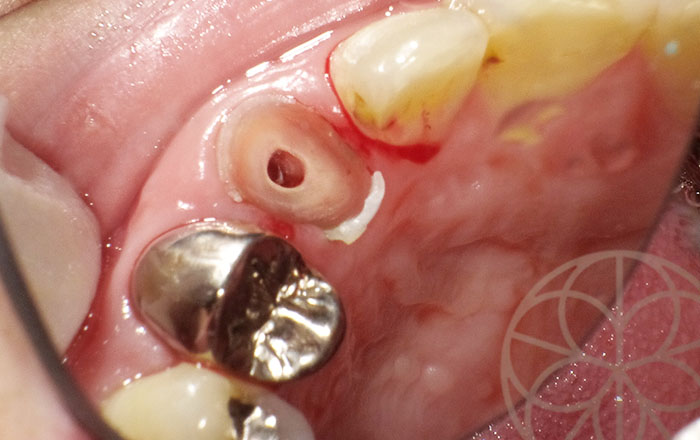

治療前状況②

右下ブリッジに問題があっため、除去してみると、右下5番目の歯に破折が見られました。この部分において、インプラント治療で加療することになりました。

患者様の希望により、悪いところはすべて加療することになったので、インプラント治療を含めた治療方針をつたえ、実施していくこととなりました。